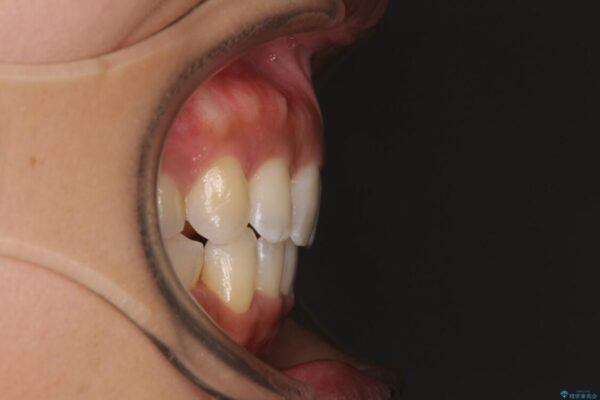

下唇が突き出るような口元の突出感が気になるとのことで来院された患者様です。

治療計画

上下顎ともに前突した歯列であったので、上下ともに左右の第1小臼歯4本を抜歯し、ワイヤー装置にて矯正治療を行うこととしました。

治療前

• 抜歯矯正で唇を閉じやすく 目立たないワイヤー装置 治療前画像